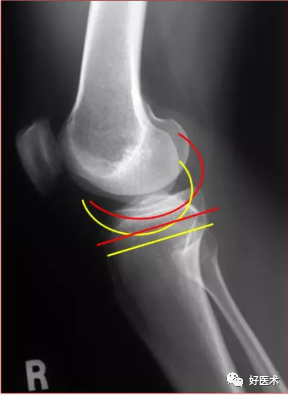

对应的X线表现:

侧位

图解股骨远端解剖要点

股骨内外髁区别

内侧髁更远 内后髁更小外侧髁更近 外后髁更大